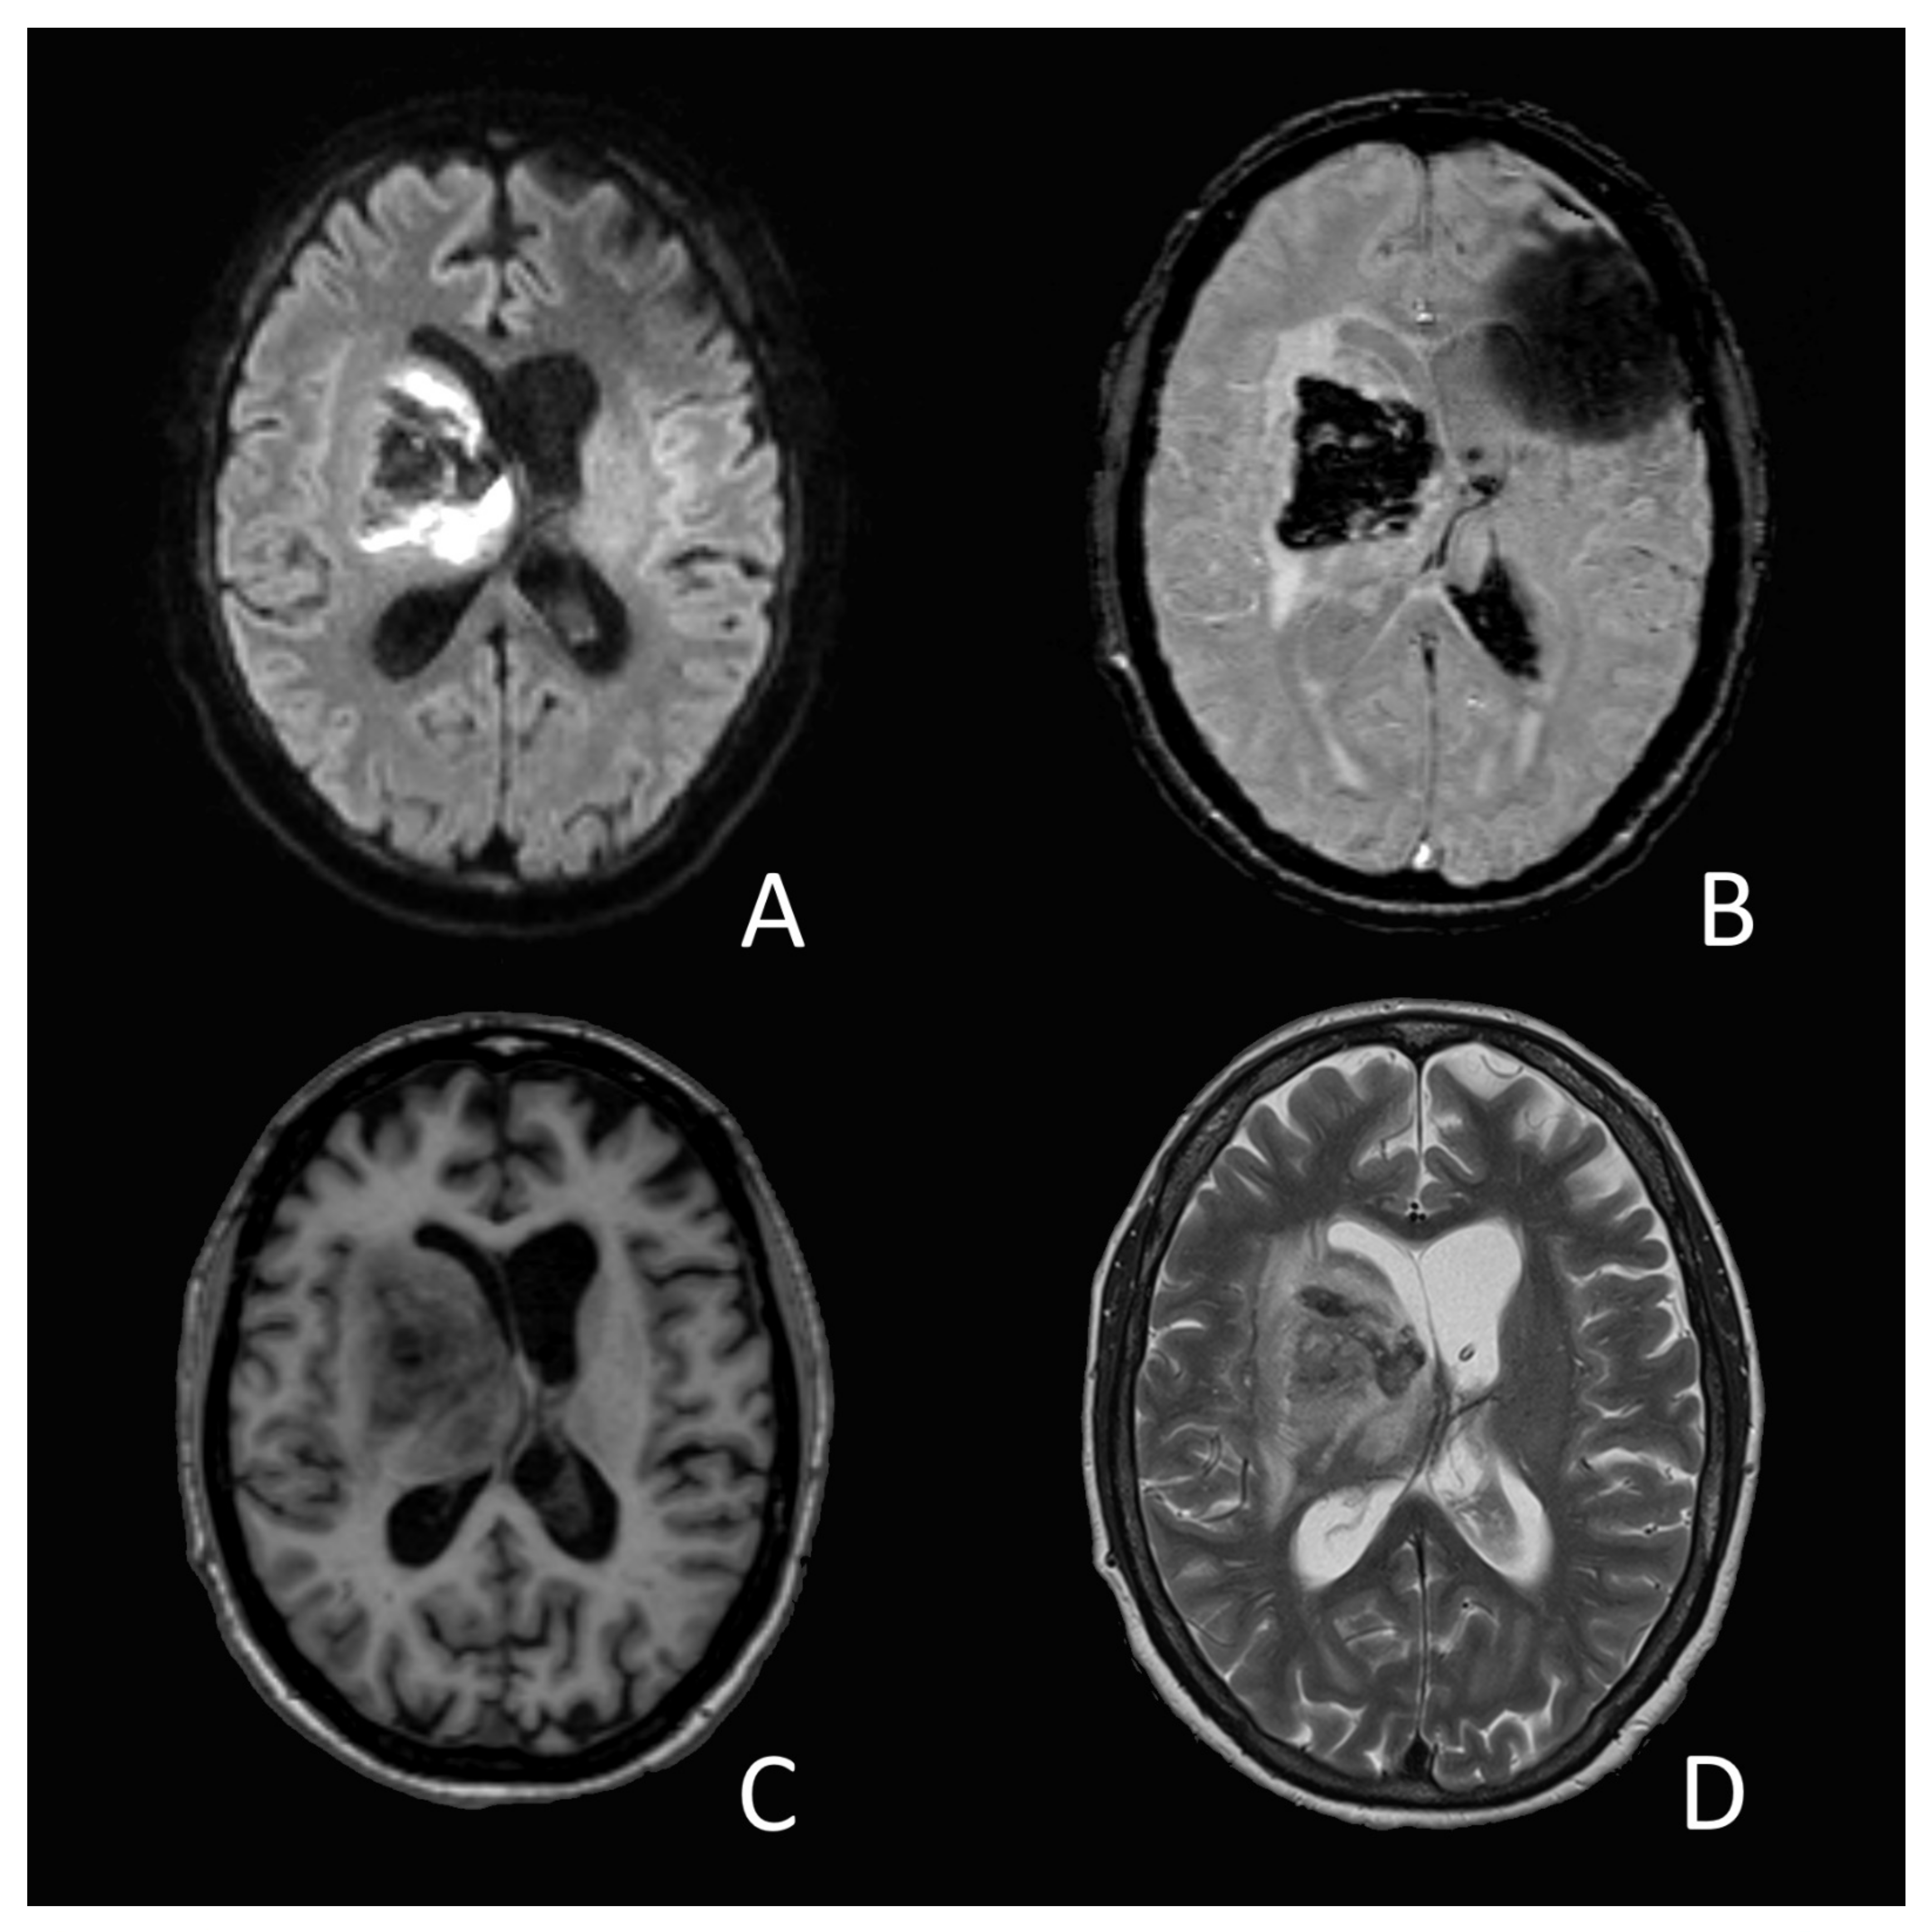

On the 14th day of hospitalization, she suddenly developed an anisocoria and a right sided hemiparesis. The MRI showed an acute intracerebral hemorrhage in the right-sided basal ganglia and thalamus (Figure 1). The source of the bleeding could not be determined, nor did the images present any vascular malformation. A coagulation analysis showed increased D-Dimer-levels (3874 ug/L), low platelets (83 G/L), a prolonged prothrombin time with an INR of 1.23 and a slightly elevated level of fibrinogen (4.06 g/L). A lumbar cerebrospinal fluid analysis showed a slight pleocytosis (7 M/L) as well as elevated protein-(3.06 g/L) and glucose (4.83 g/L) levels. SARS-CoV-2-RNA could not be objectified.

Figure 1. Cranial MRI one day after ICH diagnosis. (A) Diffusion weighted imaging (DWI) with b = 1000 s/mm2; (B) Susceptibility weighted imaging (SWI); (C) T1-weighted MRI; (D) T2-weighted MRI. Partially diffusion-restricted, T2-inhomogenous, T1-iso-/-hyperintense intracerebral hemorrhage within the right basal ganglia with subsequent midline shift and compression of the right lateral ventricle and of the third ventricle (not included in the pictures). The susceptibility artifact in picture (B) (left side, fronto-temporal) is related to the EVD-implantation. In the same picture, a significant blood collection can be seen in the occipital horn of the left lateral ventricle. Microbleeds could not be objectified.